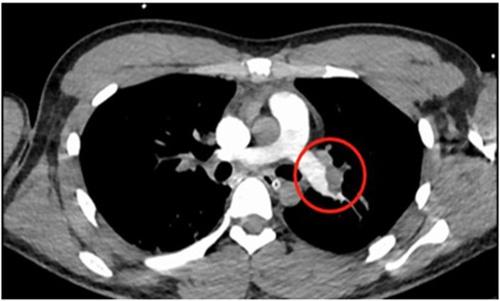

之后出現(xiàn)了第3次心臟的驟停,醫(yī)生按壓了三分鐘之后才恢復(fù)自主心率,被送入ICU進(jìn)行對(duì)癥的治療,在血管造影等各項(xiàng)檢查之后通過(guò)檢查報(bào)告,能夠看到是肺栓塞。7月31日凌晨小韓大動(dòng)脈搏活動(dòng)消失,第4次心臟驟停,醫(yī)生在靜脈上推出腎上腺素,恢復(fù)自主心率。

這是小韓病情極為危重,專(zhuān)家認(rèn)為是危重型的血栓性肺栓塞診斷上很明確,用尿激酶已經(jīng)全身溶栓治療了。但小韓呼吸循環(huán)上改善并不明顯,必須要盡快手術(shù),肺栓塞是靜脈里面血流瘀滯成為了血塊,在脫落之后伴隨著血塊流往了肺動(dòng)脈和心臟去,只有少量血液參與交換,使全身出現(xiàn)缺氧。

最終反復(fù)研判后,對(duì)小韓行了肺動(dòng)脈造影,置管溶栓和碎栓術(shù),讓血栓攪碎后再推注尿激酶,不到一個(gè)小時(shí)就順利將雙肺的動(dòng)脈打開(kāi)了,血流恢復(fù)原本的通暢血壓血氧飽和度也快速得到改善。